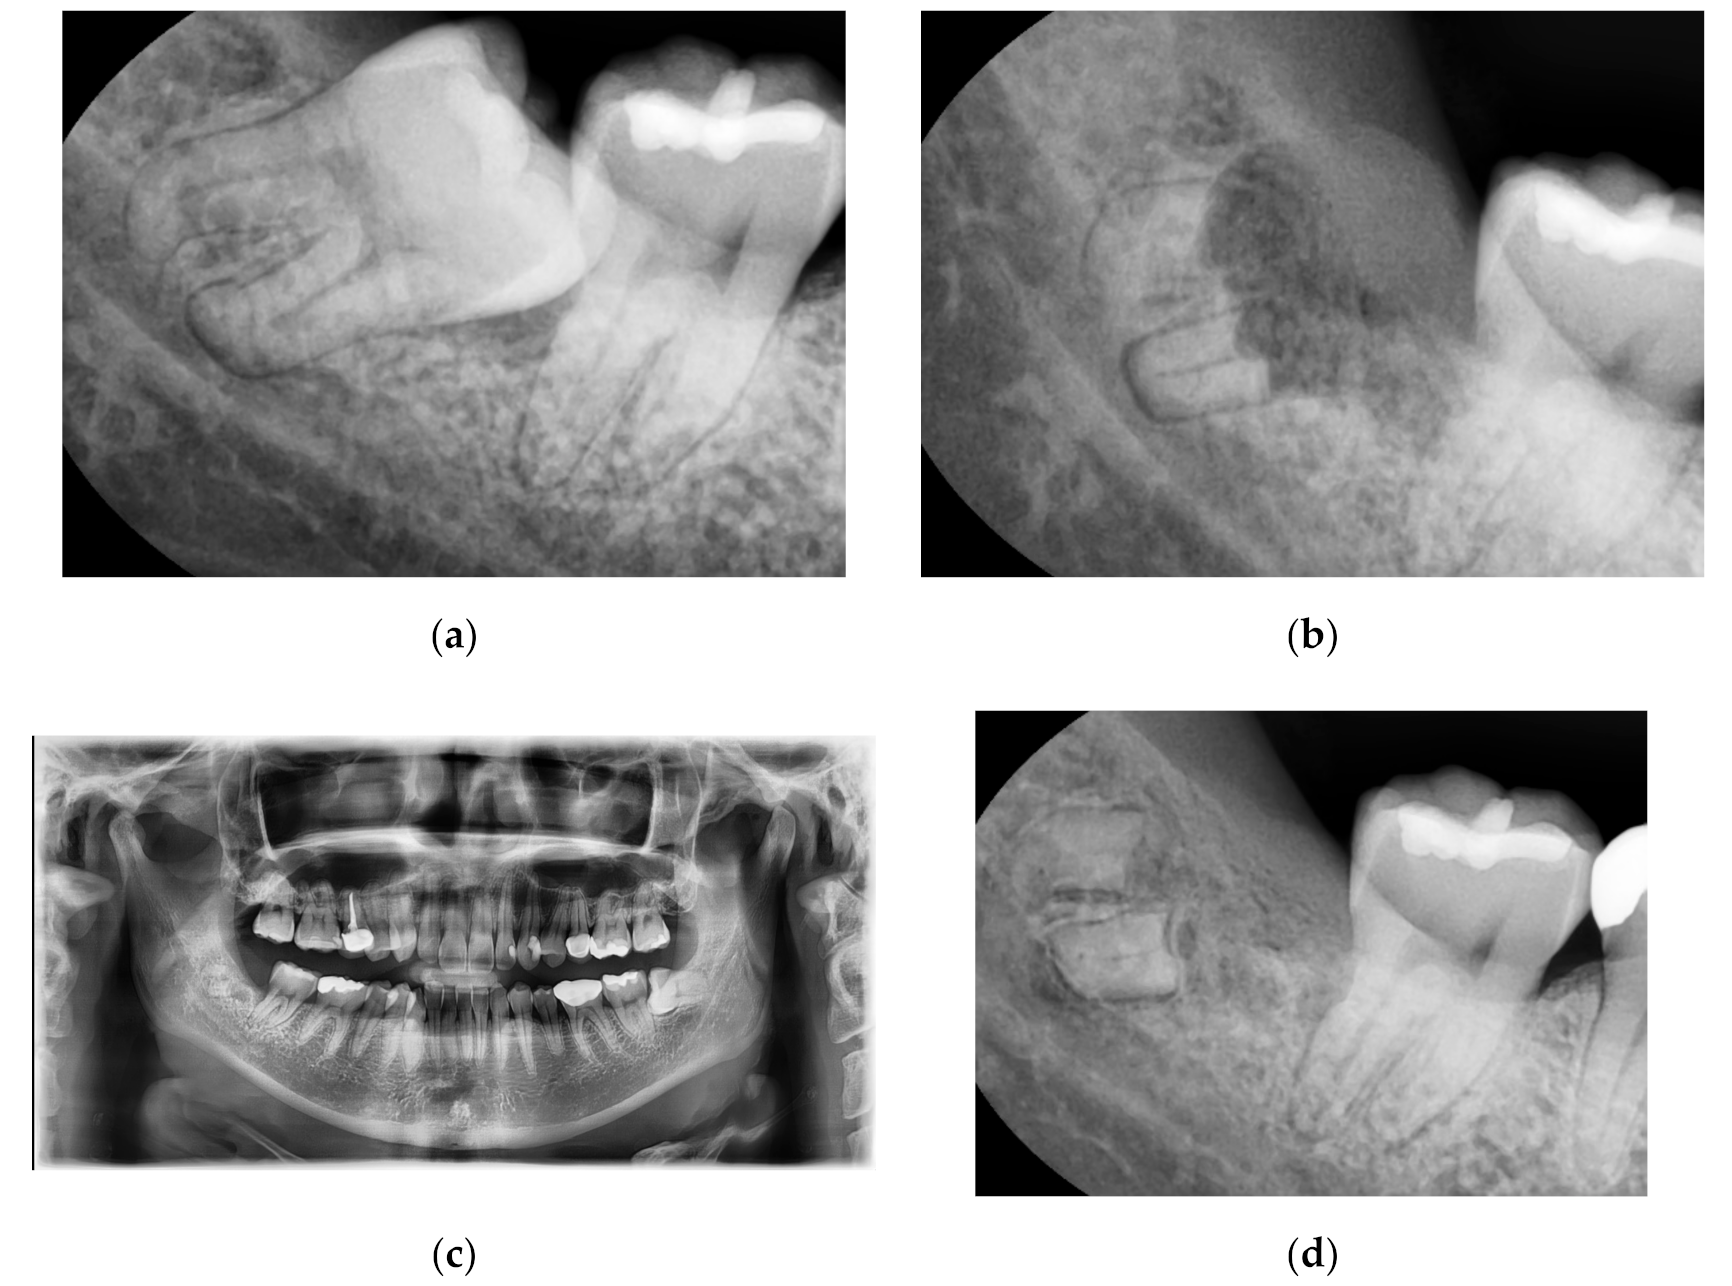

3.1. Case No. 1: Nonintentional Coronectomy

A 30-year-old male patient without systemic diseases had the right mandibular wisdom tooth extracted seven years ago due to malposition, which caused pain and sensitivity to its adjacent second molar in addition to recurrent inflammation in the gingiva around the partially erupted wisdom tooth (Figure 1a). The main clinician (Kim) noticed a dark area on the preoperative x-ray, corresponding to the apical region of the root (classified as Youngsam’ sign), thus implying that there is strict contact between the root and the lingual side of the cortical bone. To perform safe surgery, a CBCT was performed before the surgery.

The position of the apical third of the roots was evaluated using the CBCT; nevertheless, fracture of the root during surgery was not avoided. This intraoperative complication made the clinician decide to perform only coronectomy instead of complete extraction. As an example of nonintentional coronectomy, Figure 1b reveals, during suture thread removal, how the bone healed and covered the remaining region of roots after 10 days.

In Figure 1c, the OPT after 1 year from the extraction showed complete bone healing, with a re-epithelialization of the wound. The OPT was required to check the entire oral cavity and the contralateral wisdom tooth; in correspondence with the right mandibular wisdom tooth, no symptoms were reported by the patient. In Figure 1d, a radiograph after 7 years of follow-up revealed how the bone had healed completely, with no signs of inflammation around the roots. Moreover, the patient did not complain of any pain or sensitivity in the area.

Figure 1. (a): Right mandibular wisdom with pain and sensivity due to malposition. (b): X-ray after 10 days from the coronectomy. (c): OPT after one year; (d): X-ray after a radiograph after seven years of follow-up.